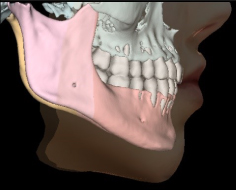

Новые инструменты программы Ez3D-i для моделирования ортодонтического лечения

Создание 3D-фото и моделирование эстетических изменений

С помощью модуля Ortho выполняется моделирование процесса перемещения элементов зубочелюстной системы при помощи данных 3D-реконструкции и 3D-сегментирования костей и зубов. Каждое перемещение на виртуальной модели протоколируется и может быть сохранено как отдельное лечение.

Дистальное перемещение нижней челюсти

Перемещение отдельных зубов

Ортогнатическая хирургия

При невозможности помочь пациенту без ортогнатической хирургии, ортодонт может выбрать пути удлинения нижней челюсти с тем, чтобы нормализовать прикус и устранить диспропорцию лица. А с помощью инструмента прогнозирования мягких тканей продемонстрировать результат виртуально.

Сегментирование кости нижней челюсти вертикальным надрезом

Нормализация прикуса

Прогнозирование мягких тканей при совмещении данных 3D реконструкции и 3D-фотографии